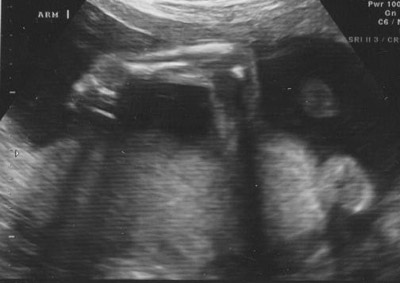

An arm and hand: